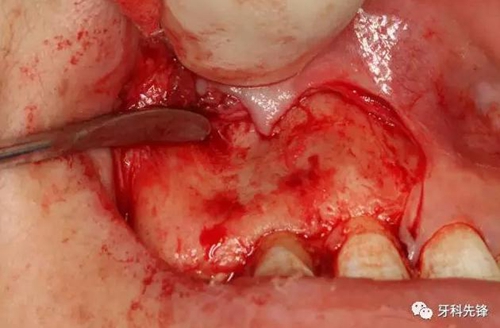

圖8.超聲骨刀去除囊腫上方的骨壁。

圖9.去除部分唇側(cè)骨板、顯露完整囊壁。

圖10.囊壁完整顯現(xiàn)。